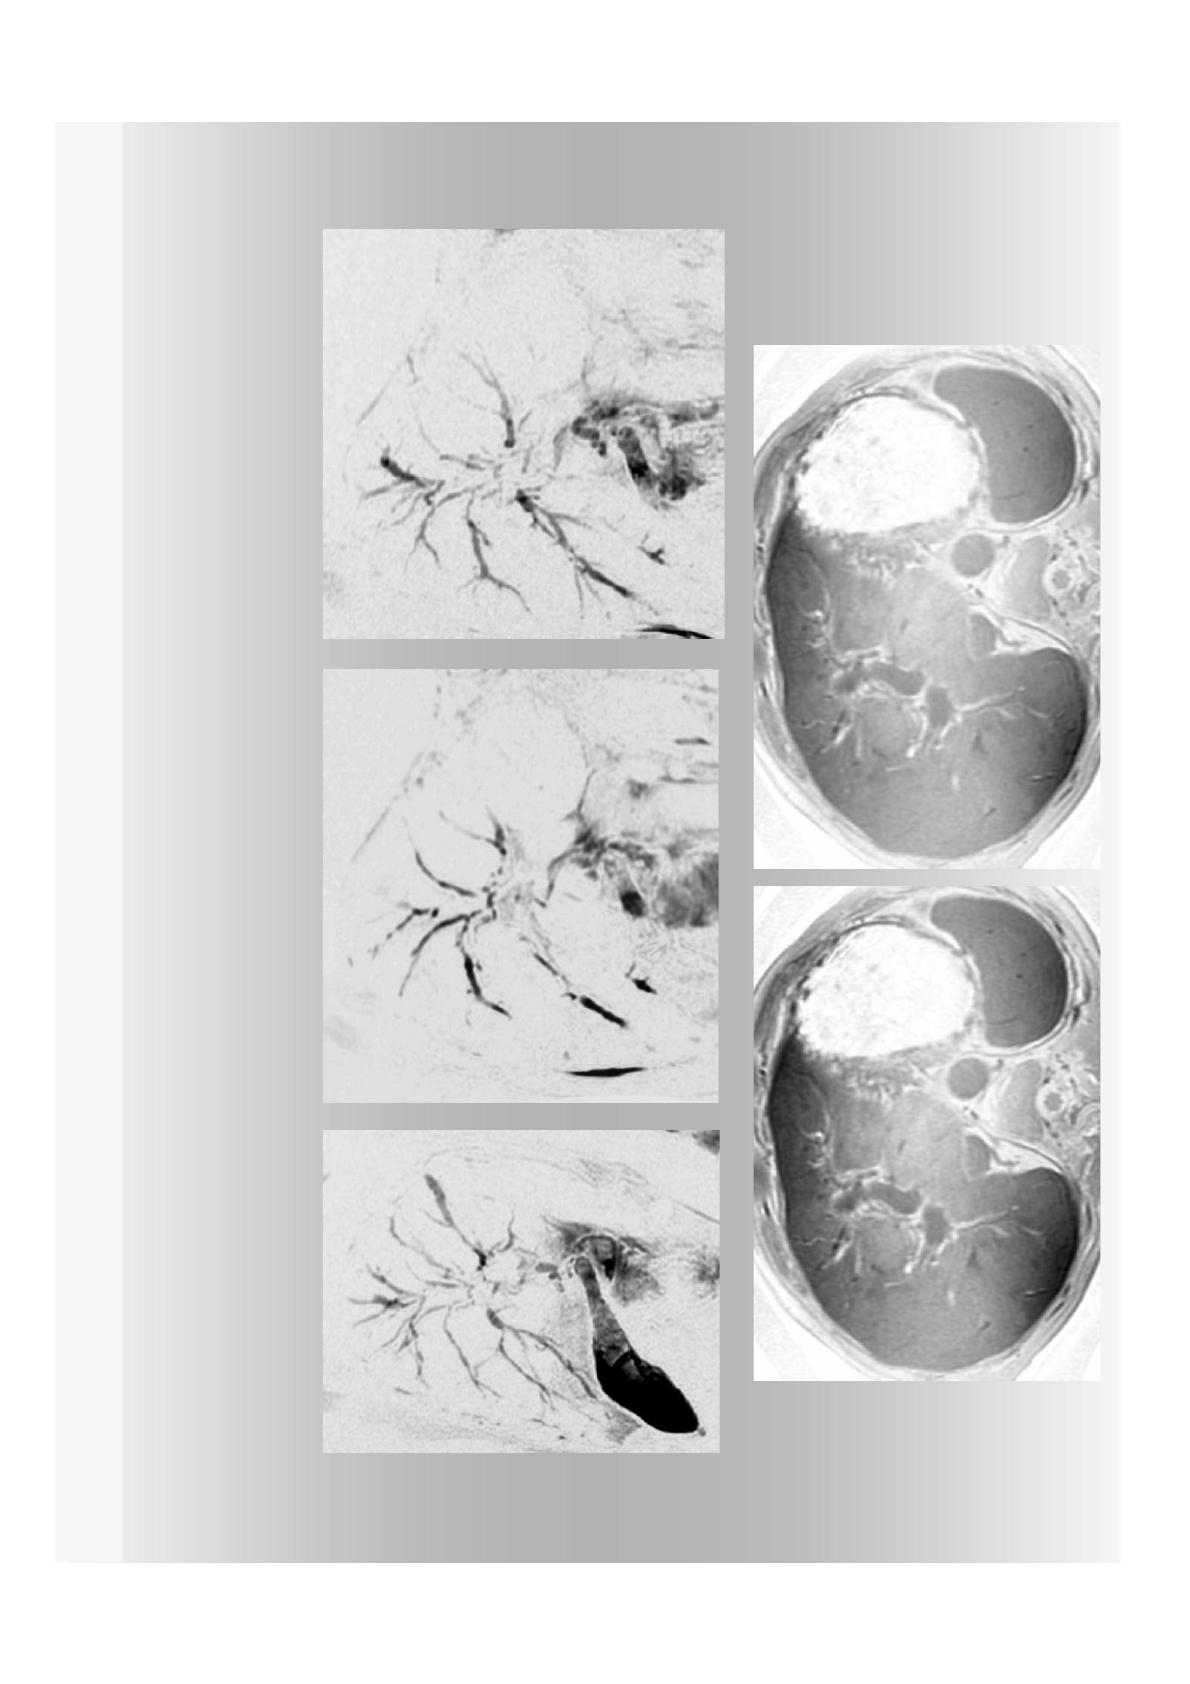

Protocole IRM

Exploration de l’ensemble des VBIH

Séquences sur l’ensemble du parenchyme hépatique

en axial ou frontal

Radiaires autour du cholédoque sont insuffisantes

pour étude des anomalies des VBIH